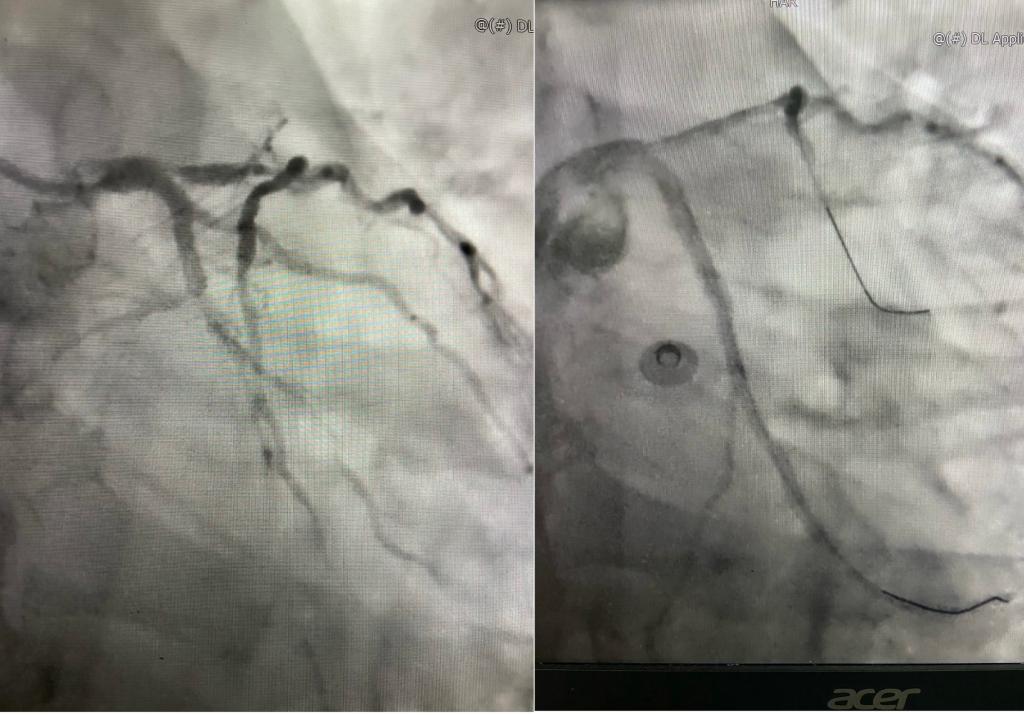

董新主任医师团队与急诊科ECMO团队充分讨论、与家属积极沟通后,决定在ECMO+IABP支持下行PCI术。在充分的备血、备白蛋白、药物维持血压等术前准备后,11月13日,急诊科裴红红主任医师调派ECMO团队内经验丰富的组员,携ECMO设备在最短时间抵达导管室,再次与董新主任医师、邓捷主任医师的手术团队确认手术方案、操作细节与流程,制定应急预案。14:00,VA-ECMO顺利运转。随后邓捷主任医师带领张明医师、苏力德医师开始实施PCI术。14:26导丝到达前降支、回旋支远端,14:30回旋支2个支架顺利释放,14:33前降支2个支架顺利释放,术中无并发症出现。看着射线下因为重新得到血流灌注而鲜活起来的心影,所有人悬着的心放下了一半。为保障ECMO顺利撤机、进一步帮助术后患者心功能恢复,植入IABP为围术期继续保驾护航。术后患者未诉不适,生命体征平稳,感染、血细胞破坏、下肢动脉缺血等术后并发症未见出现。不日,患者将好转出院。

回旋支术前、术后

入院EF0.2、术后EF0.55